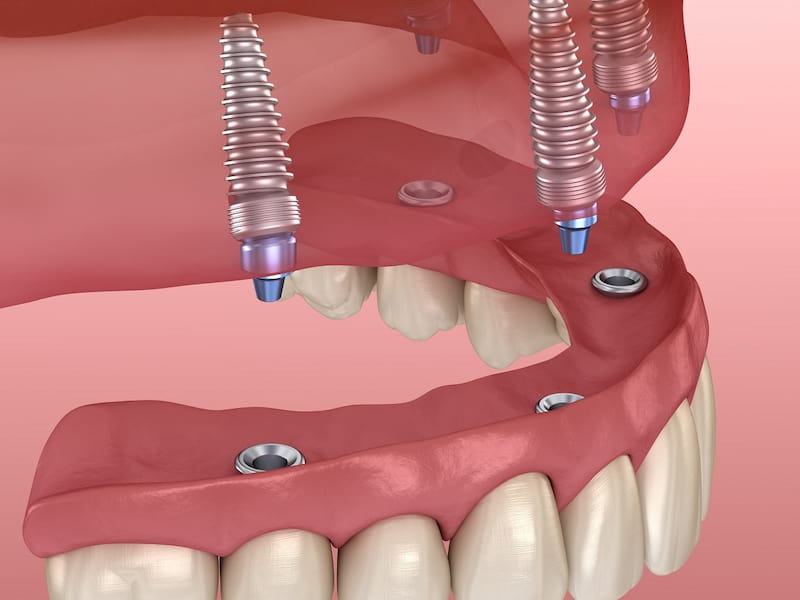

در حوزه زیبایی چهره، یکی از راههای محبوب برای بهبود شکل فک و دندانها، استفاده از ایمپلنت فک کامل میباشد.

ایمپلنت فک کامل

مشخصات ایمپلنت فک کامل

ایمپلنت فک کامل، راهی عالی برای جایگزین کردن دندانهای گمشده است و باعث تقویت قوس های فکی و بهبود خط بندی نیز میشود.